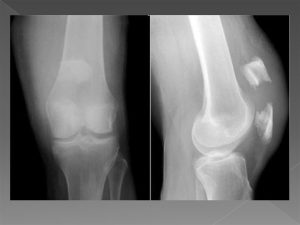

Диагноз выставляется на основании анамнеза, данных клинического осмотра и рентгенограмм в 2 проекциях.